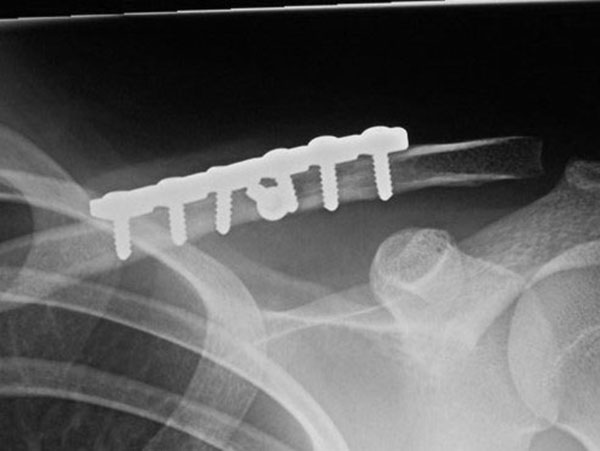

Generally all displaced fractures of the distal clavicle require surgery to increase the incidence of union. In my practice, the operation is performed by realigning the bones back to their original position using a plate and screws on top of the bone. The advantage of fixing them with a plate and screws generally means that you can start to move the arm a lot quicker and to also decrease the incidence of non-union.

How is the Operation Done?

The operation is performed with the patient under a general anaesthetic, in other words, completely asleep, and a small 3-4 cm incision is made under the collarbone, at the end of the shoulder. The fractured bone ends are exposed and put back into position using a plate and screws as shown below.

Click an image to enlarge

This fixation also needs reinforcement using special sutures around the plate and around the bone next to the clavicle called the coracoid process. The sutures are used to decrease the deforming forces from your shoulder muscles. In the majority of cases, in my hands, the operation is extremely successful resulting in the bone healing and the return of near normal function. In a small number of cases, the plate needs to be removed if it irritates the patient under the skin.